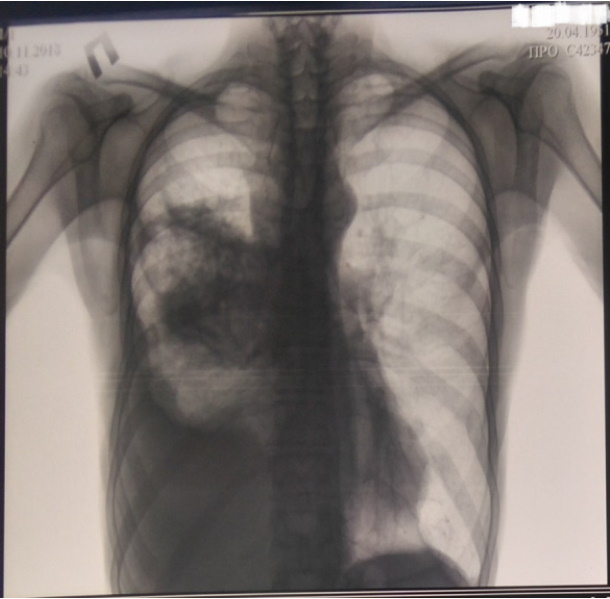

На контрольной рентгенограмме грудной клетки от 26.11.2018 г. снова отмечается ухудшение прозрачности справа в средних и нижних отделах, сохраняется субтотальное интенсивное затемнение за счет ателектаза средней и нижней долей, а также жидкости и плевральных наложений. Слева в проекции «головки» корня легкого плотная очаговая тень 10×15 мм. Легочный рисунок деформирован за счет явлений пневмосклероза. Корень слева не расширен, структурный. Диафрагма и синусы слева контурируются. Средостение смещено вправо (рис. 7).

Рис. 7. Рентгенограмма органов грудной клетки от 26.11.2018